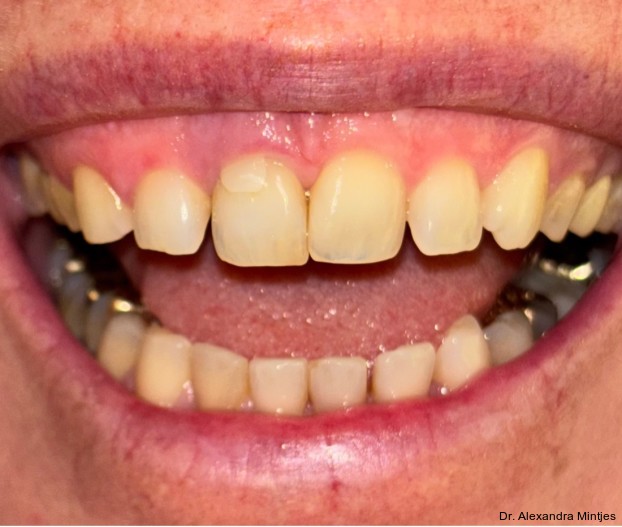

Bei der Erstvorstellung zeigte die vorhandene Füllung einen deutlichen Randspalt, war verfärbt und nach apikal hin insuffizient. Klinisch präsentierte sich ein dicker gingivaler Phänotyp mit ­harmonischer Weichgewebsbalance, jedoch bestand distal eine lokalisierte, entzündliche Zahnfleischtasche (Abb. 1). Es war zu vermuten, dass das nekrotische bzw. resorptive Hartgewebe nicht vollständig entfernt worden war. Auf dem DVT wurde das Ausmaß des Defekts deutlich. Zu­dem ließ sich eine deutliche apikale Aufhel­lung nachweisen, die Patientin war jedoch beschwerdefrei (Abb. 2).

Die Diagnose lautete eine invasive zervikale Resorption Klasse 3 nach Heithersay. Dieses Sta­-dium beschreibt eine tiefe Resorption mit Ausdehnung in das koronale Dentin und das zervikale Drittel der Wurzel, ohne dass die Pulpa vollstän­dig involviert ist. Solche Läsionen gelten als prognostisch kritisch und führen in der Regel zu einer extraktiven Therapie.